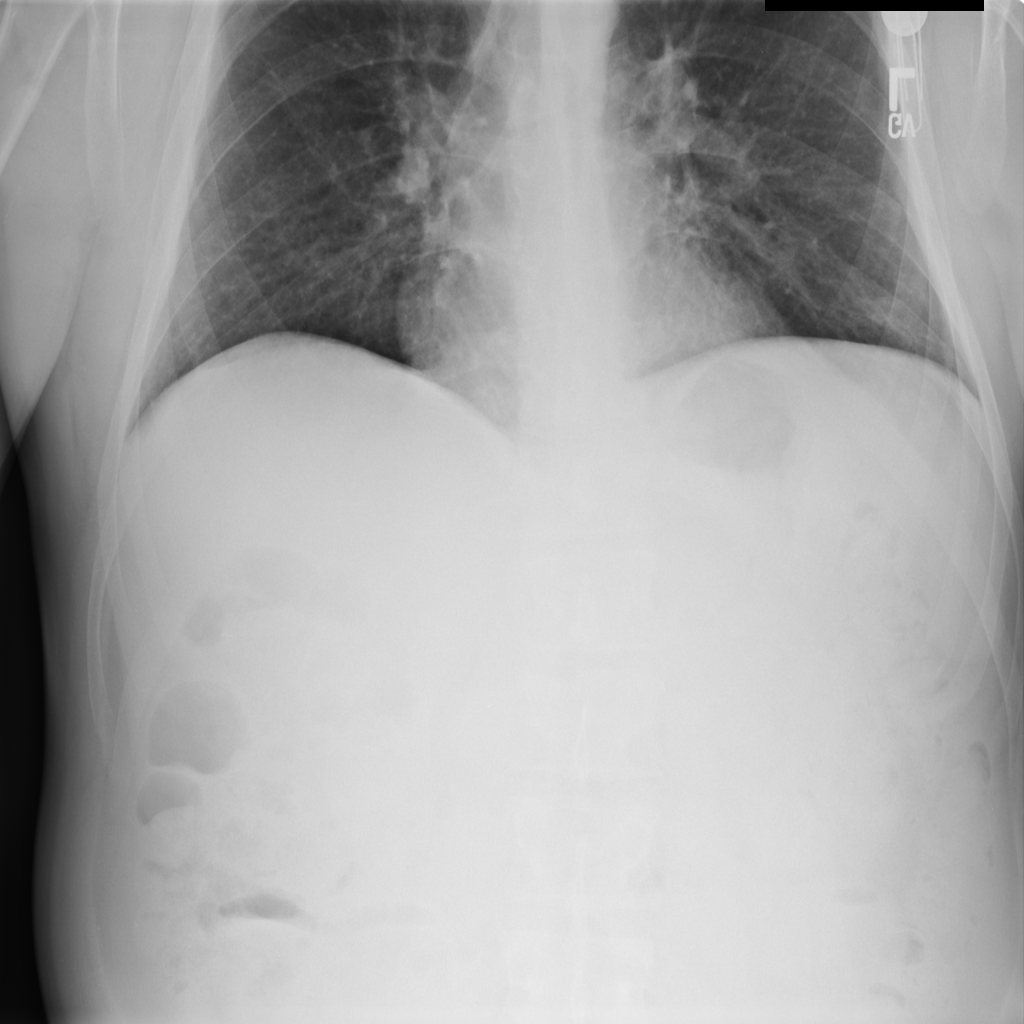

PAT-B733 · IMG-000Consolidation

PAT-B733 · IMG-000

PA